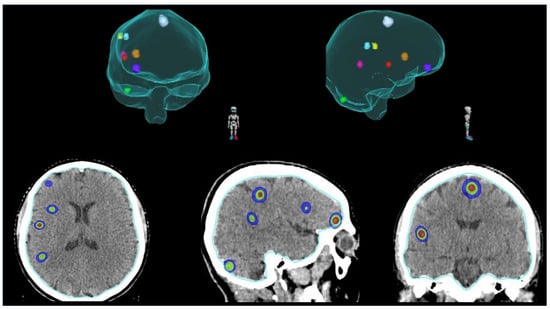

2.3. SRS for Polymetastatic BMs